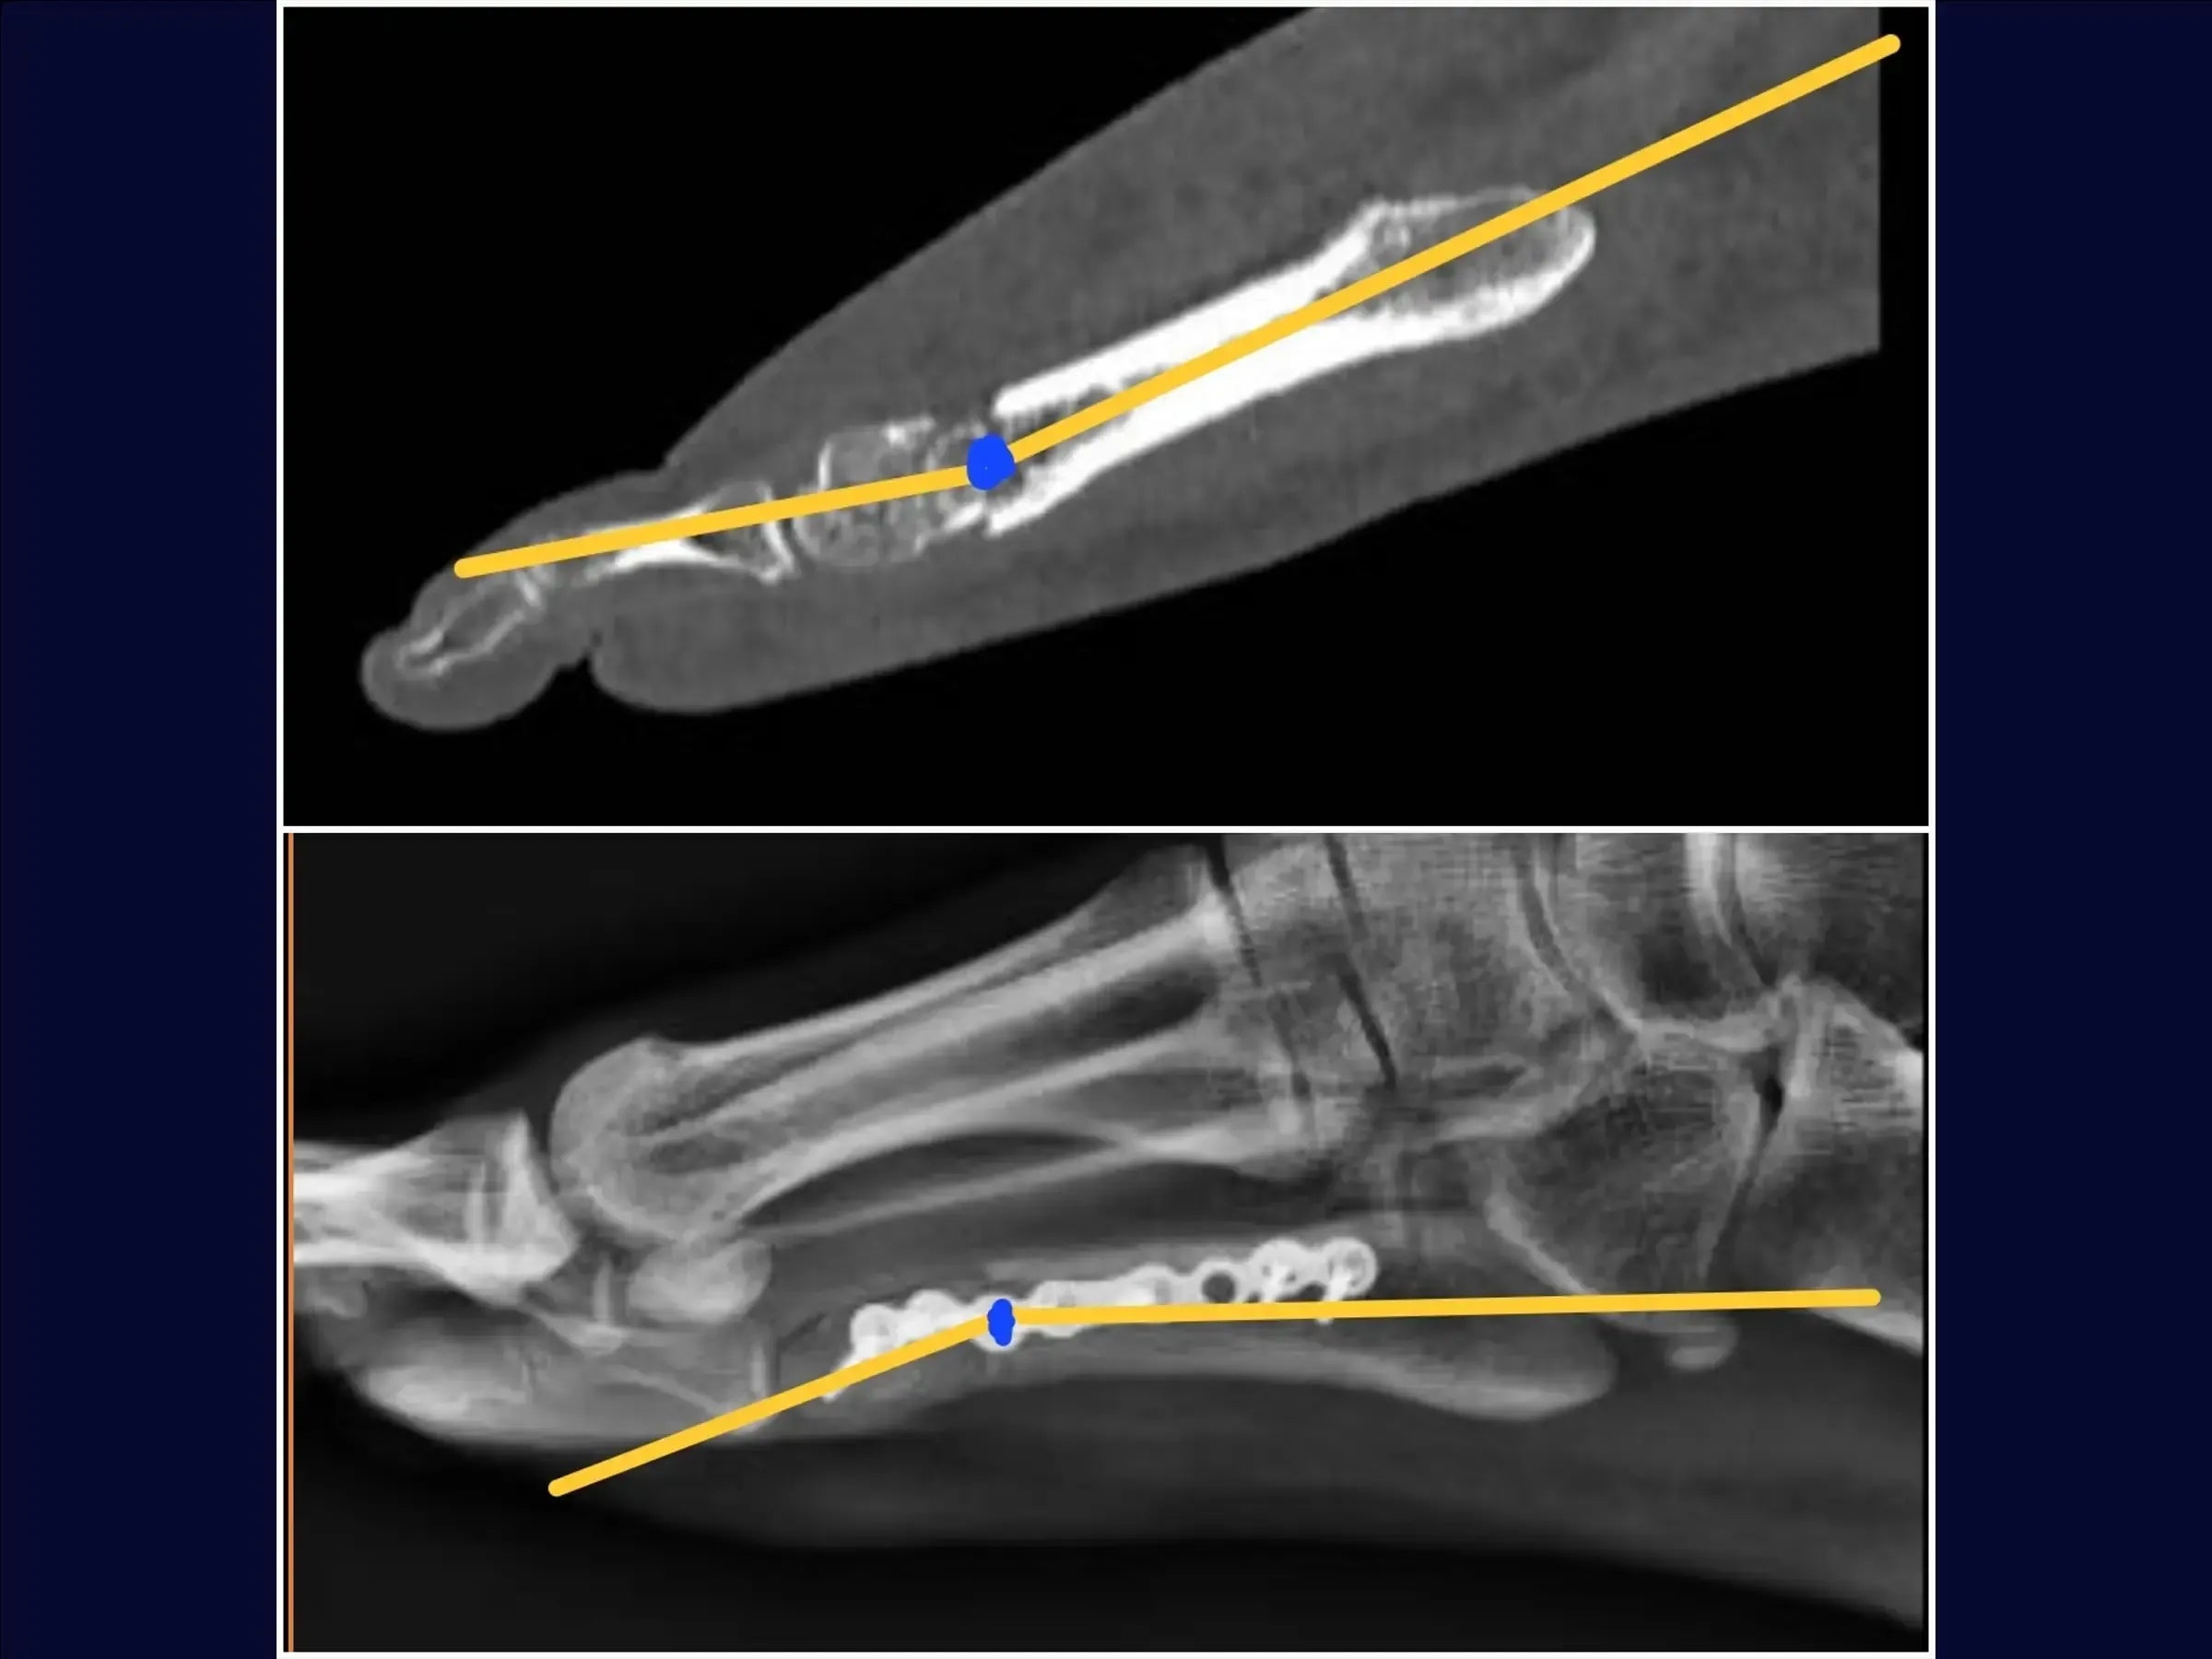

- Evaluación y planificación del acceso: análisis de radiografías para identificar la angulación de la fractura y la posibilidad de alteración de la carga de peso, metatarsalgia o disfunción de la marcha.

- Reducción de la fractura y estabilización provisional: Identificación de los vértices de la fractura, reducción bajo visualización directa con pinza de reducción y estabilización provisional con agujas de Kirschner, evitando la zona de la futura placa.